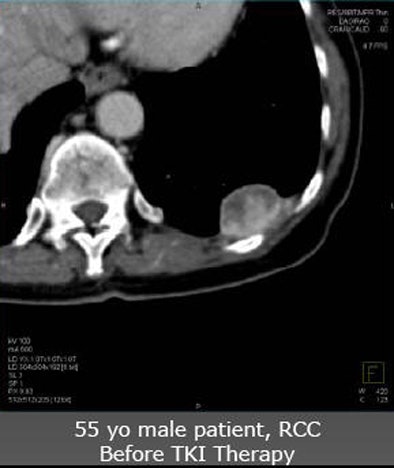

| Future studies will focus on clinical experience with angiogenic agents. In a patient with renal cell carcinoma with pleural metastasis (above), decreases in tumor perfusion are readily seen after three weeks of sorafenib antiangiogenic therapy (below). |

![]() |